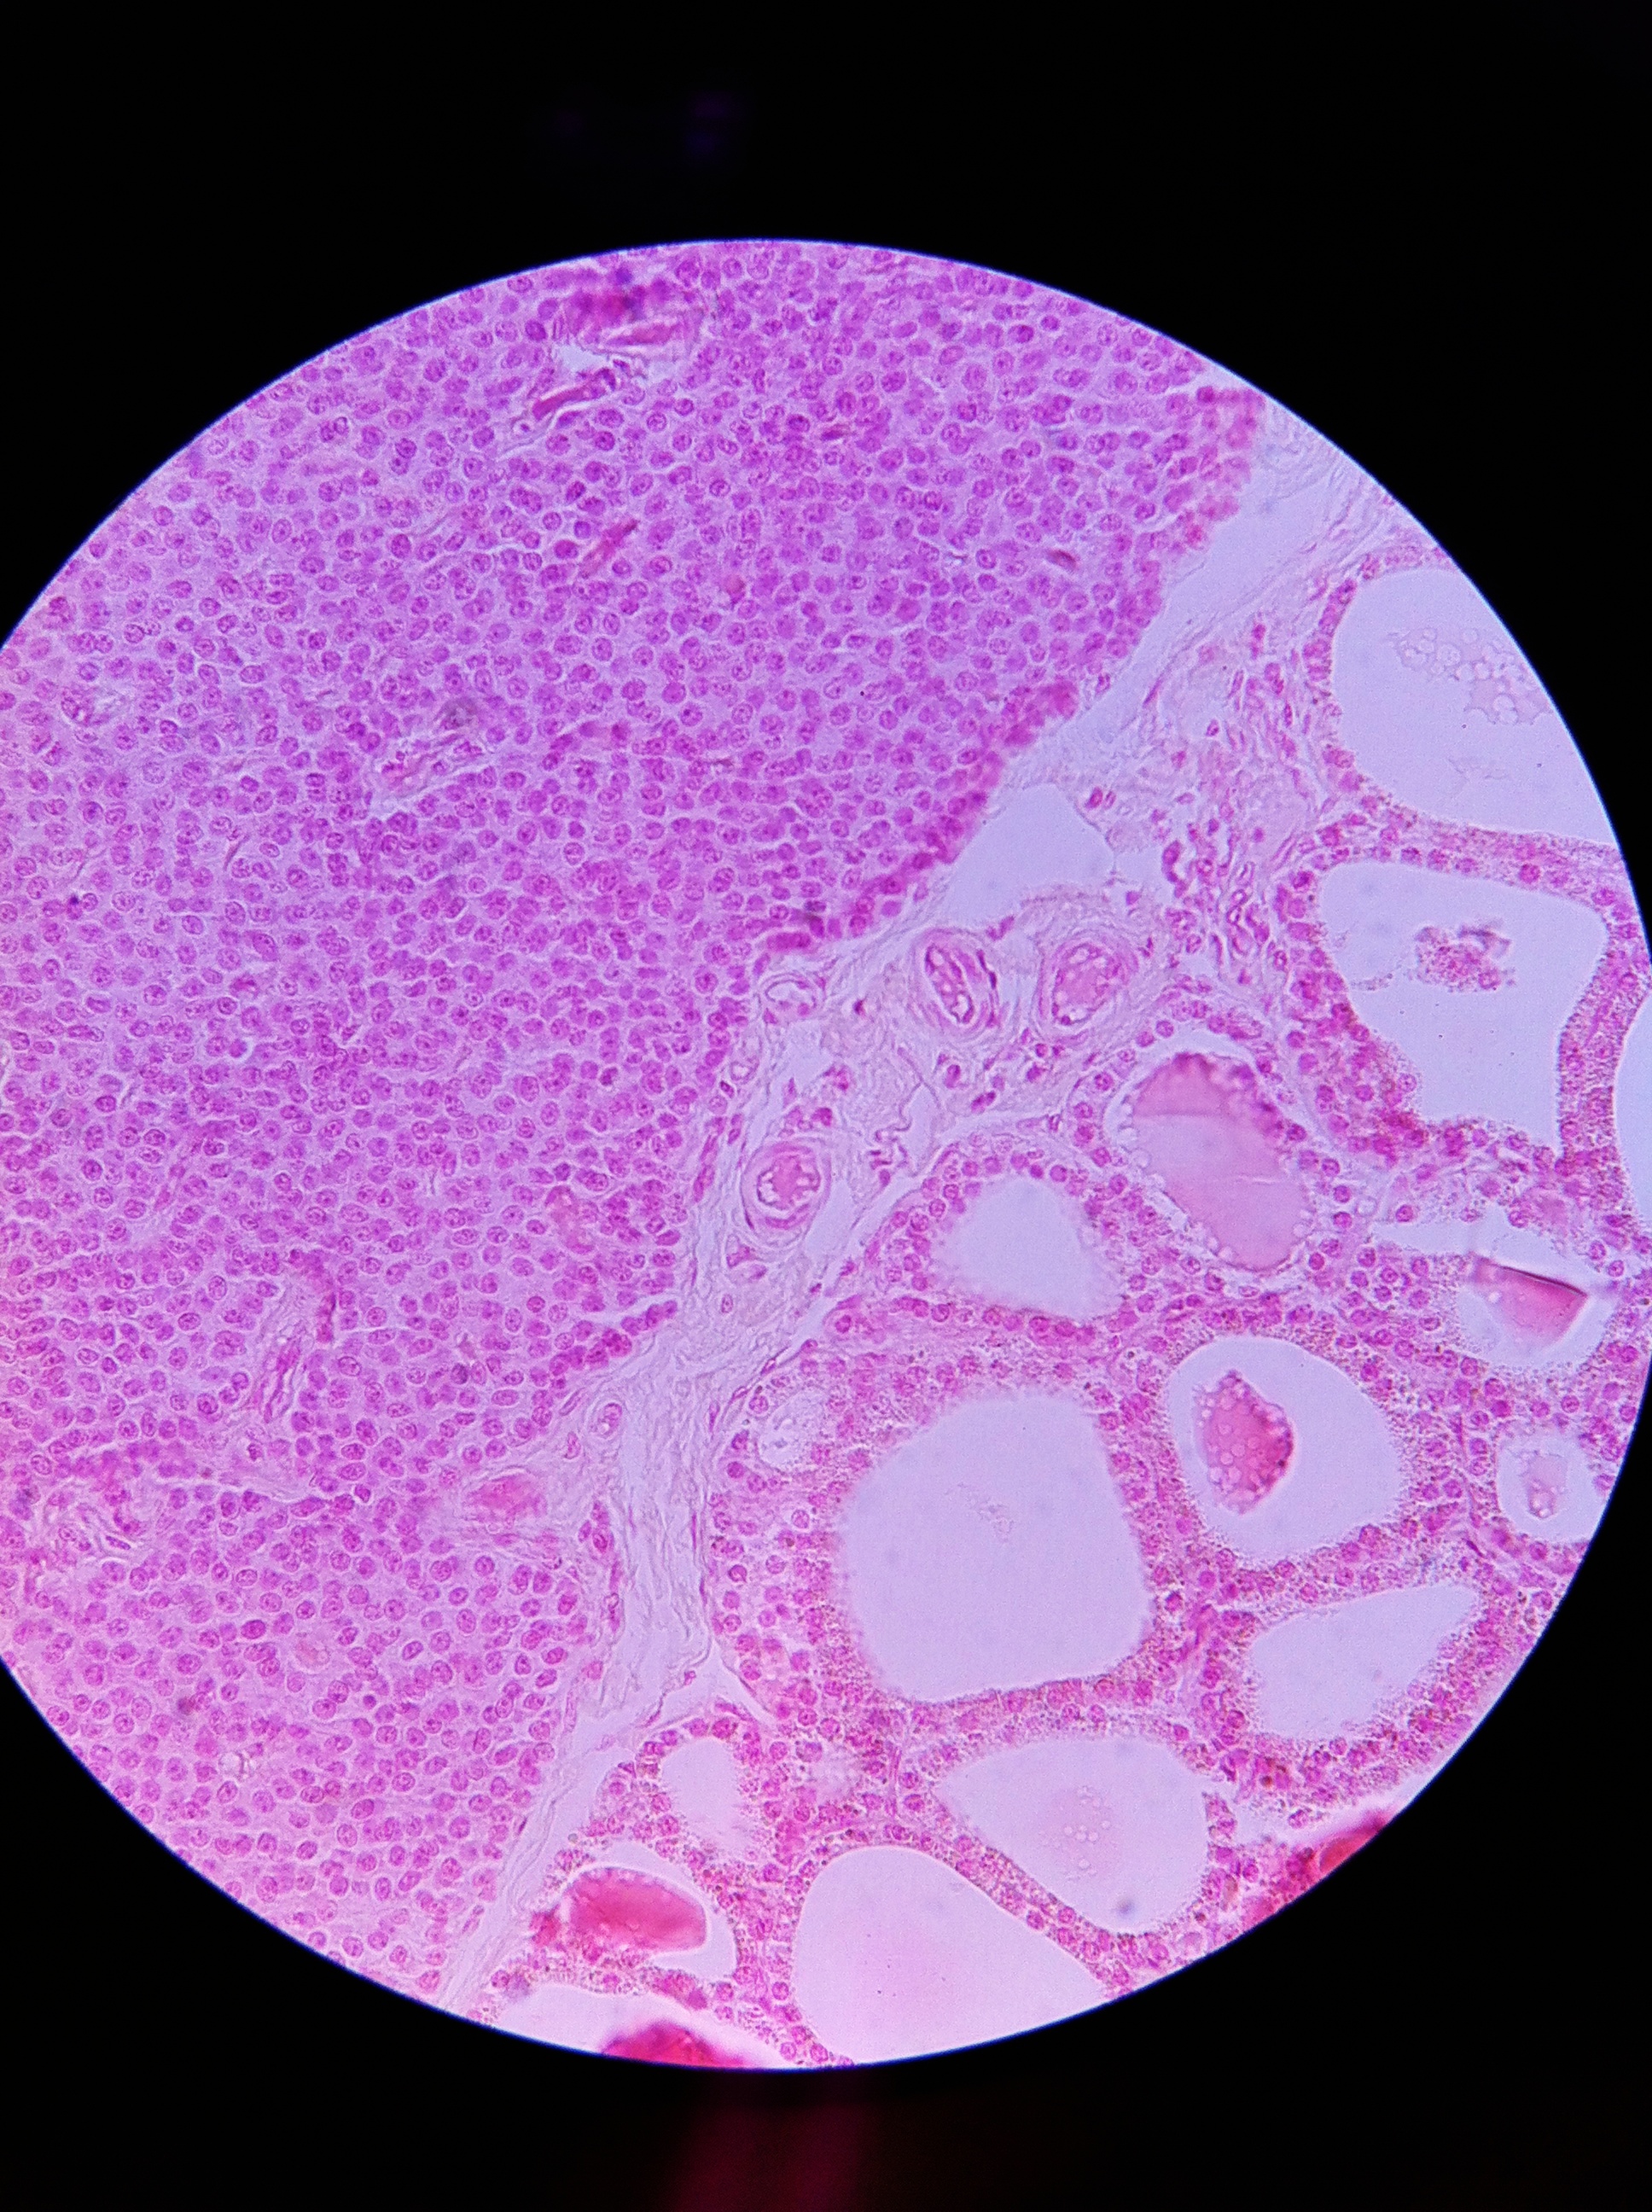

Parathyroid and Thyroid 400X